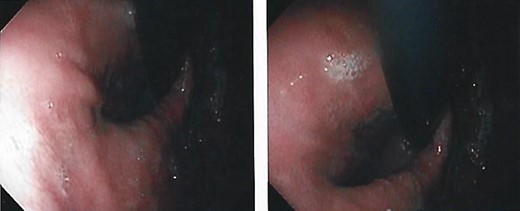

We present the case of a 21-year-old male patient, with a history of laparoscopic cholecystectomy and 3 cryoablations for Barret’s esophagus with grade III dysplasia, who presented with persistent postprandial vomiting that had caused weight loss of 11 kg in the last 2 years without apparent cause, associated with gastroesophageal reflux that has worsened over time, occasional stabbing abdominal pain in the epigastrium, painful constipation, bloody stools and steatorrhea, managed clinically and symptomatologically without improvement in the condition. On evaluation, the patient was thin, with a BMI of 17.31 kg/m2, and in paraclinics, in endoscopy (Figs 1 and 2), Barret’s esophagus and hiatal hernia; In tomography (Figs 3 and 4), an aortomesenteric angle of 17.5°, with aortomesenteric distance of 4 mm.